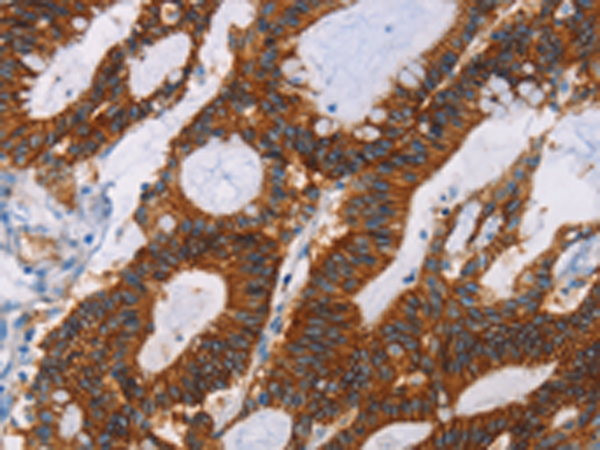

分类: 科研抗体货号: P07338别名: CLA1; SRB1; CLA-1; SR-BI; CD36L1; HDLQTL6应用: IHC反应种属: Human